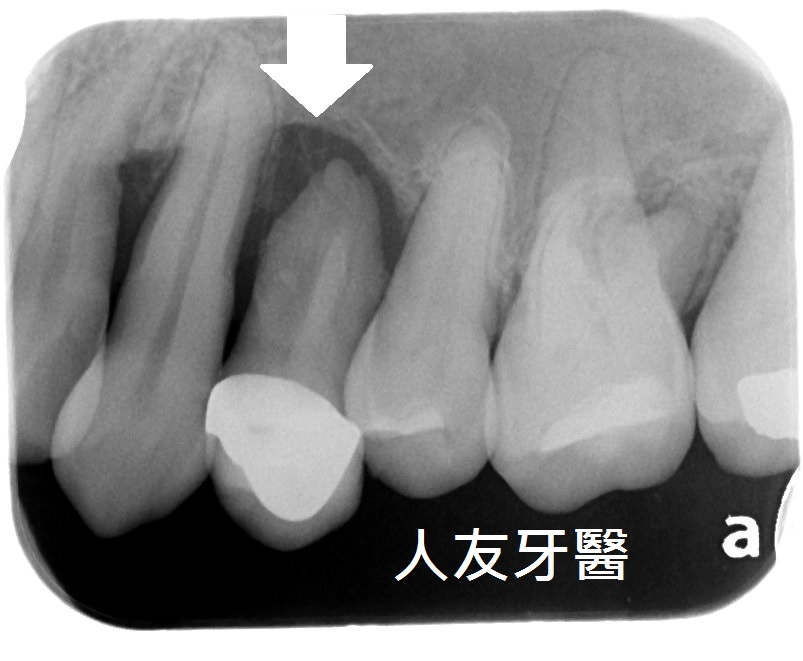

3.拔牙與骨釘:為騰出空間進行矯正,需要拔牙;骨釘用於輔助移動牙齒,初期可能會有異物感,但通常很快能適應。(下兩圖)

拔牙後放骨釘關閉空間原理與優點:

1.骨釘是植入在骨頭中的支撐點,提供穩定的錨定力量,確保牙齒移動的方向不受影響。

2.傳統矯正中移動牙齒可能造成其他牙齒跟著移動,使用骨釘可以精準控制牙齒的移動方向,讓拔牙後的縫隙能有效且正確地關閉。

3.骨釘可以大幅提升牙齒移動的效率,可能縮短矯正療程時間。

4.除了關閉拔牙空間,骨釘還能應用於骨性暴牙、嚴重深咬等情況,讓治療範圍更廣。